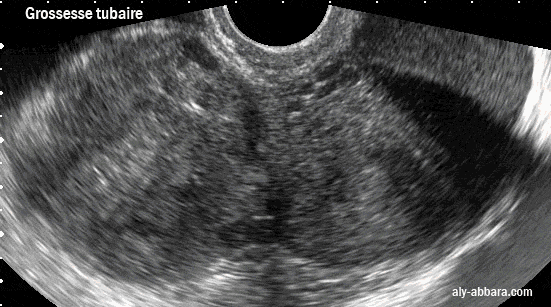

L'aspect échographique

d'une grossesse extra-utérine tubaire gauche avec un énorme hématosalpinx.

La formation de cet macro-hématosalpinx est favorisée par l'épaississement de la paroi tubaire, en rapport avec

une salpingite chronique (données de l'examen anatomopathologique de la trompe gauche)

Sur cette image la trompe gauche paraît à droite car par son poids et son volume, elle s'est déplacée vers la droite.